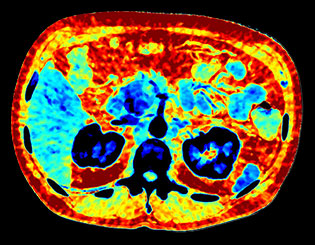

View an anatomical area using different spectral results.

Created by removing the iodine component from the image. Hounsfield Unit (HU) measurements from virtual non-contrast spectral results are comparable to true non-contrast scans for the majority of the organs, allowing VNC results to replace a true non-contrast scan.